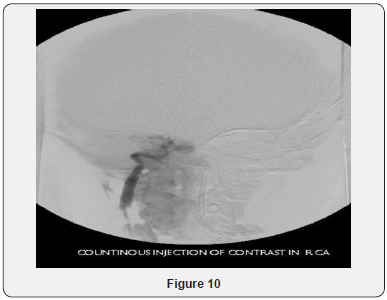

Echocardiogram Holter monitor and Eye examination all were normal. The patient underwent muscle biopsy which showed mild lipid myopathy with type 2 muscle fiber atrophy, but with no morphological evidence of mitochondrial disease. A stat CT brain showed hemorrhagic infarction and some fresh bleeding in subarachnoid space (not older than 3 days), possibly on the basis of ischemic lesions, considering the further hypodense lesions in the parasagittal area on bi-occipital and parieto-occipital regions, more extended on the left side (Figure 4). The neurosurgery team was notified, but it was determined that the patient has poor prognosis and is not candidate for surgery. Gradually, the patient developed respiratory distress and was transferred to the intensive care unit and required mechanical ventilation. He was monitored continuously by EEG. At that time, he showed subclinical seizures originating from the posterior head region, right side more than left. A burst suppression pattern was established, but during the burst period he was having multifocal spikes and polyspikes. Brain MRI showed massive hemorrhagic infarction of non-vascular distribution pattern involving the posterior occipito-parietal, region with brain stem area and cerebellum (Figures 5-9) and a lesion extending to the temporo-parietal region (Figures 5,7). Cerebral angiography showed multiple territorial hemorrhagic infarctions, with no blood entering intracranially in a case of massive intracranial edema, suggesting brain death (Figure 10). Using homozygosity mapping followed by whole exome sequencing, we identified a homozygous mutation of APOA1BP that caused lethal infantile leukoencephalopathy. The patient continued to deteriorate, then died at the age of four years.